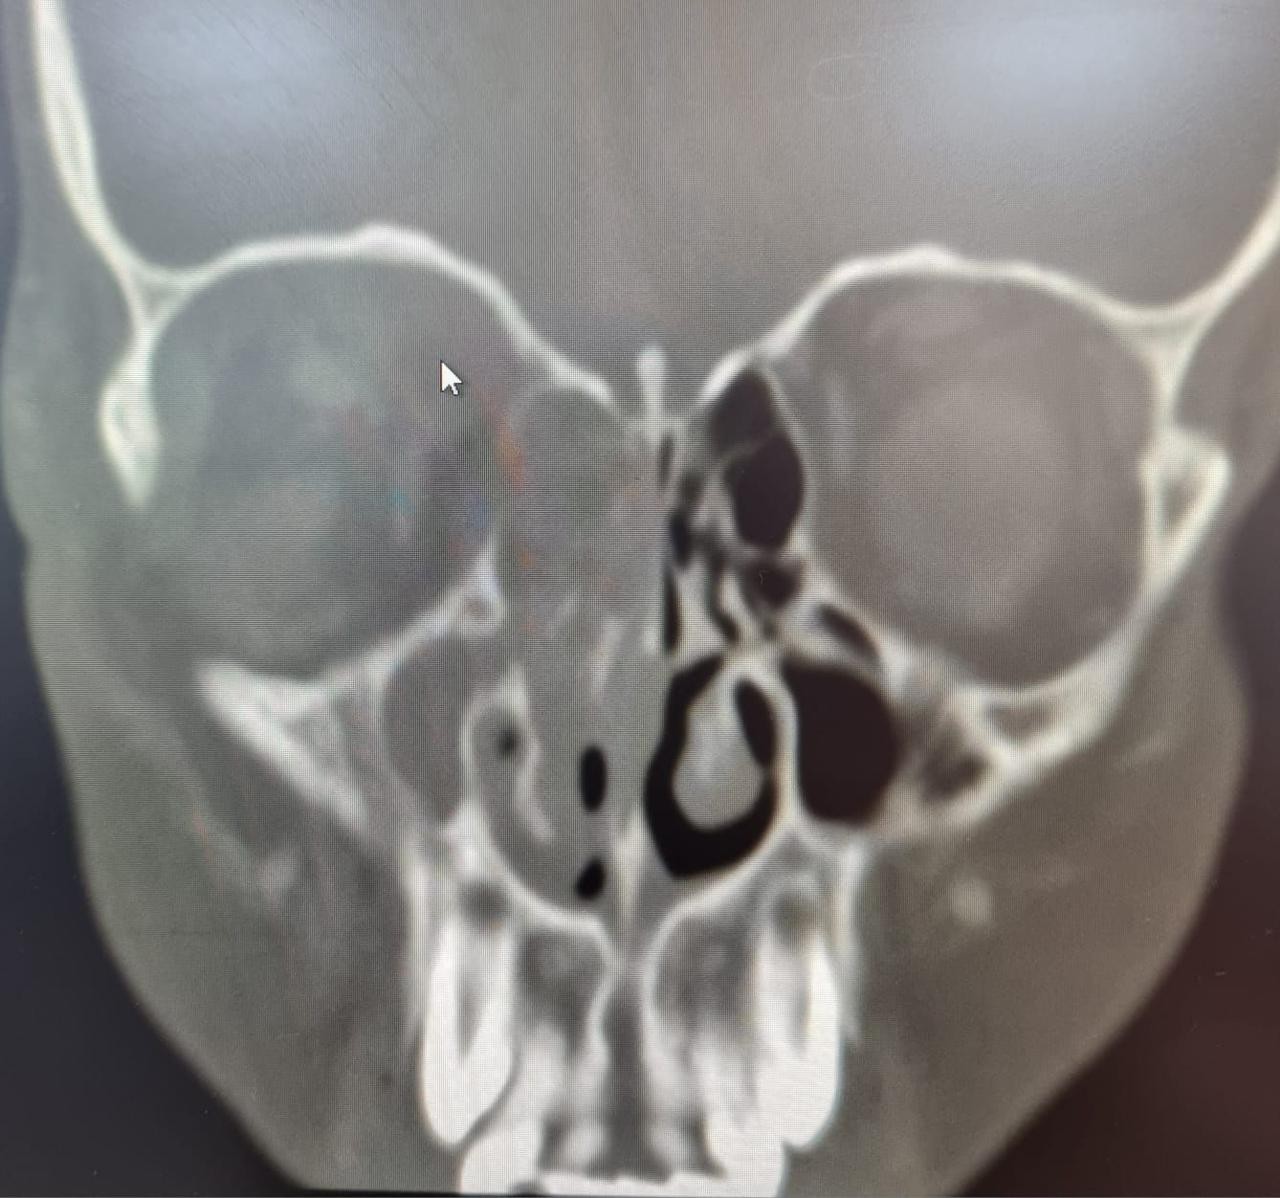

وأكدت الصحة في جدة أن المريض حضر إلى طوارئ مستشفى الملك عبد العزيز كحالة انقاذ عضو يشتكي من ألم حاد و احمرار و انتفاخ شديد في العين اليمني منذ خمسة أيام ، و تم عمل الفحوصات و الأشعة المقطعية اللازمة التي أظهرت التهاب شديد في الجيوب الأنفية من الجهة اليمني أدت إلى وصول خراج (صديد) لمقلة العين اليمني.

وبينت أن الفريق الطبي المعالج قرر إجراء تدخل جراحي عاجل وإجراء عملية دقيقة بالمنظار للجيوب الأنفية و تنظيف كامل لكل الاحتقانان و الالتهابات و الخراج (الصديد) لجميع الجيوب الأنفية للجهة اليمني و الجهة الداخلية للعين اليمني ، ليتم بعدها نقل المريض لقسم التنويم ومتابعة الحالة من قبل الفرق التمريضية لحين استقرار الحالة وخروجها بالسلامة من المستشفى.